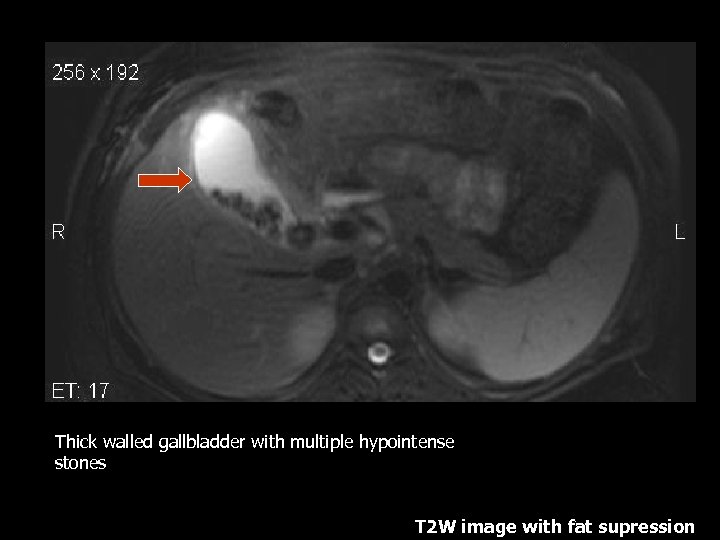

Thick walled gallbladder with multiple hypointense stones T 2 W image with fat supression

Cholecystitis • Second most common surgical condition during pregnancy(1). • 1/6000 to 1/10, 000 pregnancies(3) • Cause is usually due to cholelithiasis in >90%(3). • LFTs elevated(1). • Gad enhanced T 1 weighted images with fat suppression show high sensitivity in diagnosing cholecystitis(7).